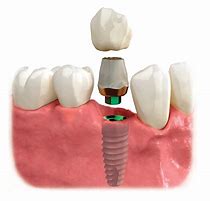

The simple or surgical removal of teeth which may utilize bone grafting to preserve the bone for a future implant. In some cases, an immediate temporary tooth or teeth can be prepared before the extraction is done to allow for a nice smile and to fill the gap.